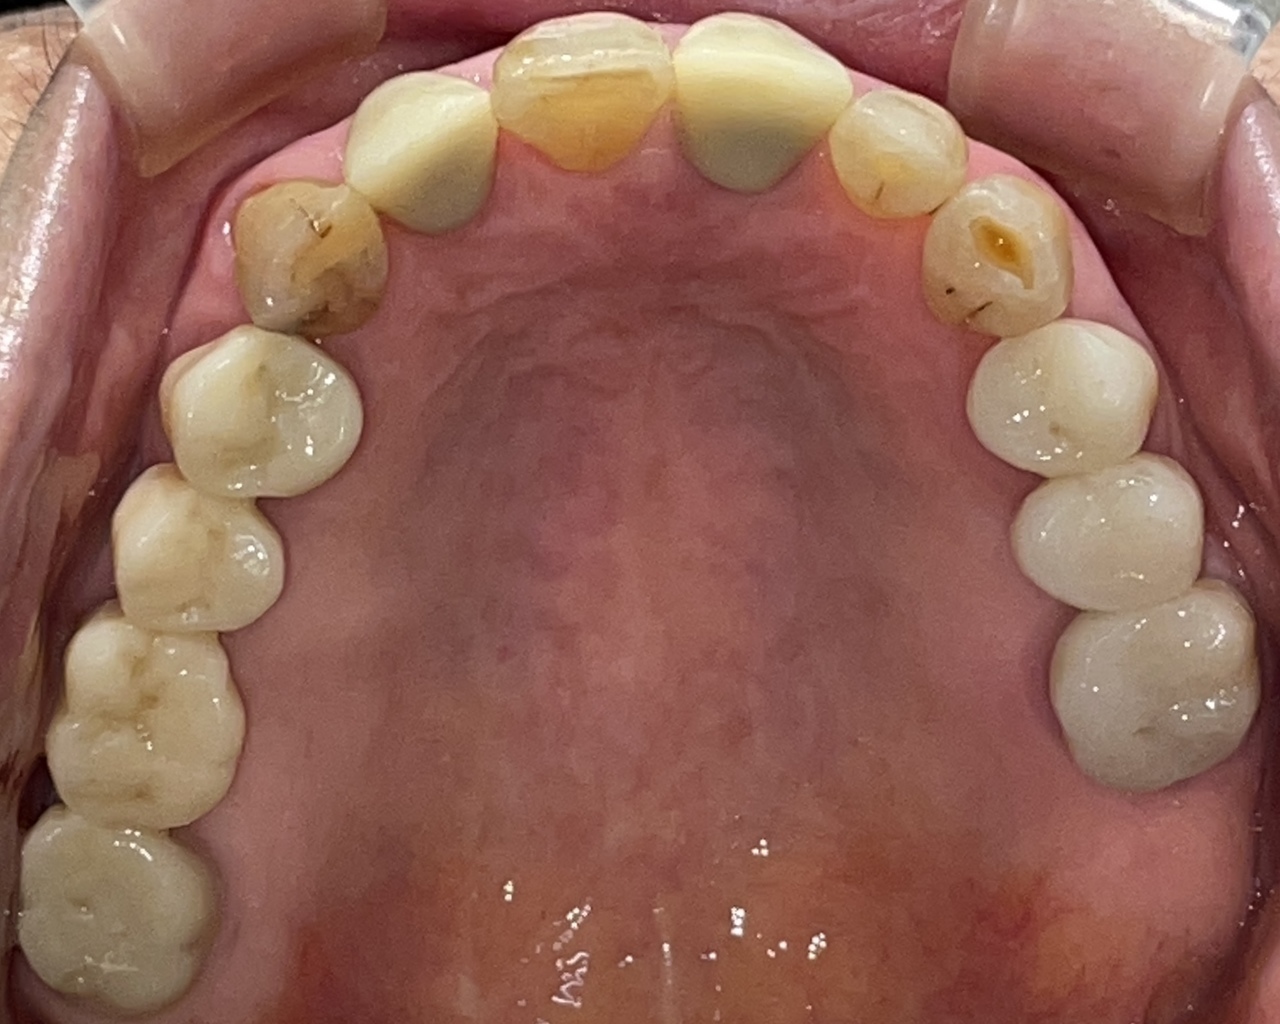

Before

After

矯正の種類 / invisalign GO

年齢・性別 / 40代男性

主訴  /  上下顎前歯の叢生

治療期間 / 12ヶ月

費用 / 簡易検査 5,000円(税別) 精密検査 30,000円(税別)

両顎マウスピース 450,000円(税別) 両顎リテイナー料 40,000円(税別)

※マウスピース交換時別途調節料5,000円(税別)

副作用 / 口内炎・歯の移動に伴う痛み・知覚過敏 ※数日で収まる場合が多いです

リスク / 後戻り防止の為、夜のみマウスピースで保定を指示